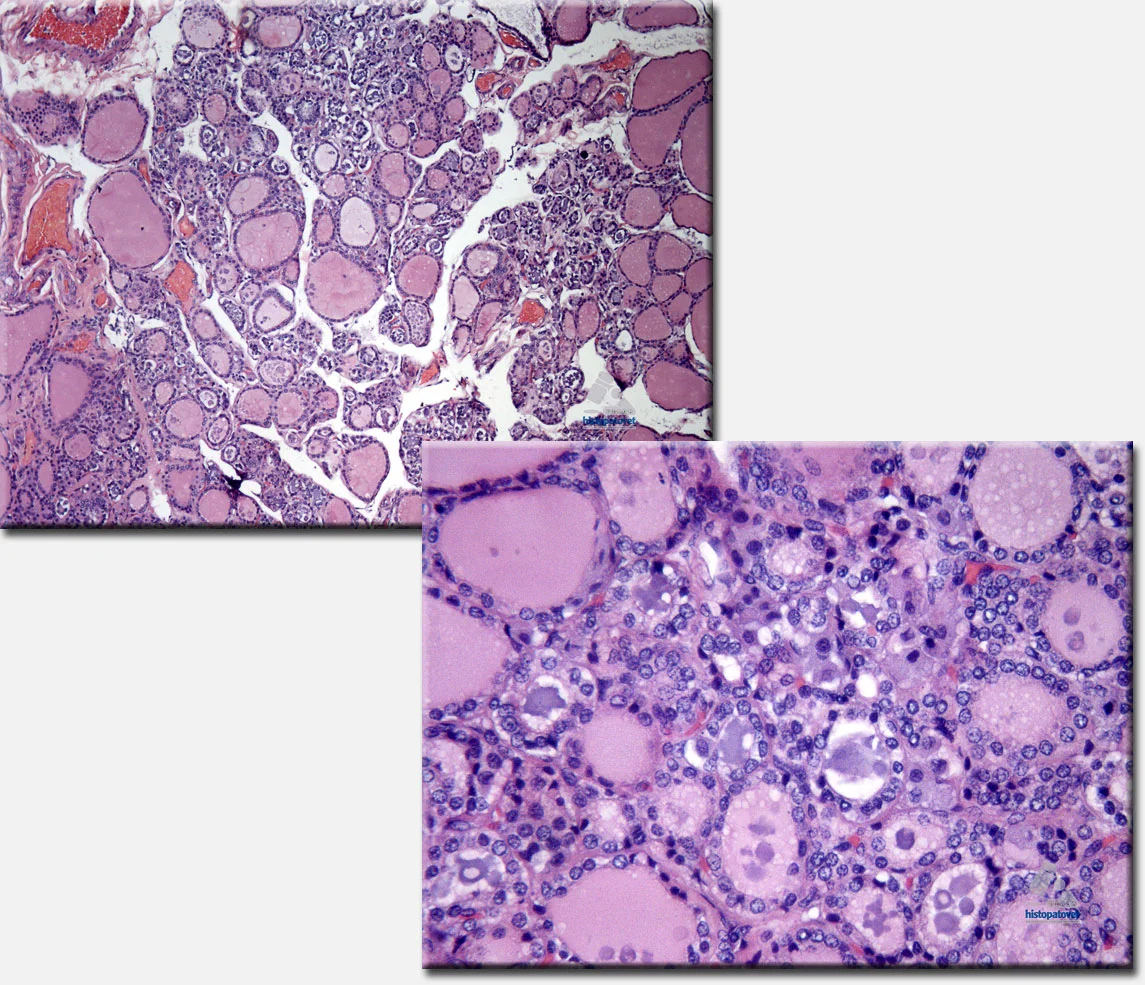

Fig. 6. Tiroides. A la izquierda(arriba), se observa varios folículos con coloide( material rosado). A la derecha un detalle. Los folículos están disminuidos de tamaño o han desaparecido. En otros folículos su contenido rosado ha sido sustituido por uno morado.CONCLUSIÓN DIAGNÓSTICA: La principal patología fue un hematoma esplénico o del bazo, el cual por razones no determinadas, quizás algún trauma previo(golpe) o por una acción espontánea, se rompió, provocando un hemoperitoneo agudo, con consecuente hipoxia/anoxia celular y muerte. Además, secundariamente había un material lipídico con presencia de un pigmento tipo ceroide, subcapsular hepático. También el bazo presentaba nódulos de gamna gandy. Adicionalmente, había una disfunción de la glándula tiroidea, (hipotiroidismo, antecedente clínico).COMENTARIO FINAL: Hay reportes de que pacientes con un hipotiroidismo pueden causar una lipidosis, sobre todo ocular y también trastornos de coagulación.